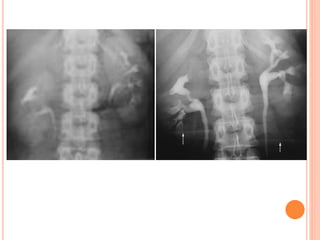

URETERS

- peristalsis.

- Stasis of contrast.

- Medial deviation.

- Lateral deviation.

- Anatomic narrowing.

- Ureter diameter (8mm).

- Filling defect.

 Medial deviation of the ureter should be considered

when the ureter overlies the ipsilateral lumbar

pedicle.

 lateral deviation should be considered when the

ureter lies more than 1.5 cm beyond the tip of the

transverse process.

URETERS - peristalsis. - Stasisof contrast. - Medial deviation. - Lateral deviation. - Anatomic narrowing. - Ureter diameter (8mm). - Filling defect.

• 53.

 Medial deviationof the ureter should be considered when the ureter overlies the ipsilateral lumbar pedicle.  lateral deviation should be considered when the ureter lies more than 1.5 cm beyond the tip of the transverse process.

• 54.